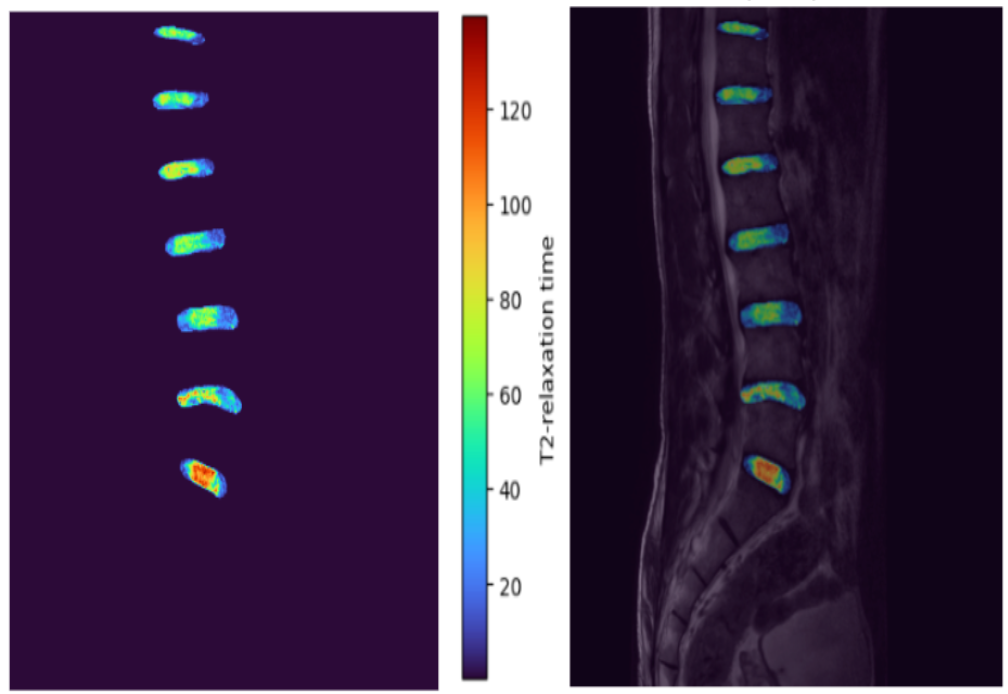

T2 Mapping for Disc Hydration Estimation

This project aims to create a T2 map from multi-echo MRI signals to estimate the relaxation times of intervertebral discs, providing an approximate indication of the hydration levels of the discs.